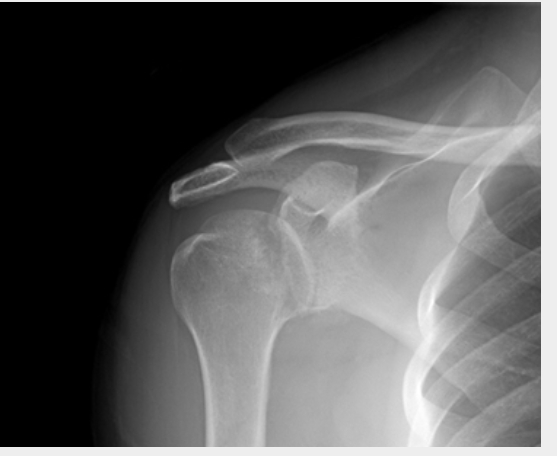

Scapular Y x-ray view showing an anterior fracture dislocation of the shoulder and fracture of the greater tuberosityPersonal collec